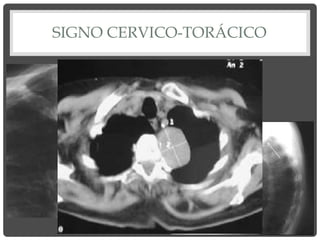

SIGNO CERVICO-TORÁCICO

• “Si una lesión torácica está en

contacto anatómico con partes

blandas del cuello, su borde

contiguo desaparecerá”.

• Masa con borde superior

definido, que termina a nivel de

las clavículas, tiene

LOCALIZACIÓN

INTRATORÁCICA Y ANTERIOR.

indefinido o que termina por

encima de las clavículas, se

encuentra en cuello y torax

(mediastino medio o posterior).